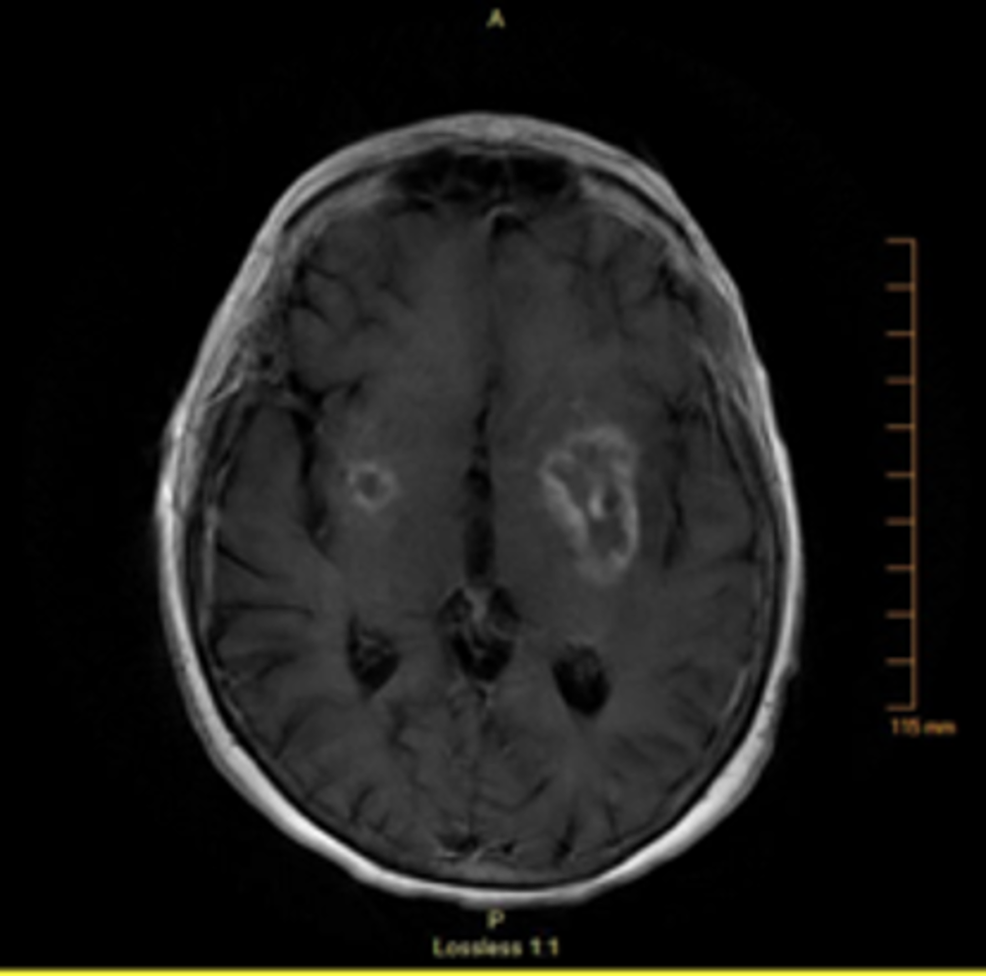

View Effects Of Rheumatoid Arthritis In The Brain Pictures. It typically results in warm, swollen, and painful joints. Rheumatoid arthritis and brain fog.

Alternative therapies in health and medicine. Rheumatoid arthritis (ra) is a common chronic inflammatory autoimmune disease characterised by an inflammation of the synovial joints leading to ra is associated with significant morbidity, including pain and disability. But many people with ra say they also have to deal with symptoms in a 2009 study of mice, researchers found evidence that swelling in the body's tissues, or inflammation, may be to blame.